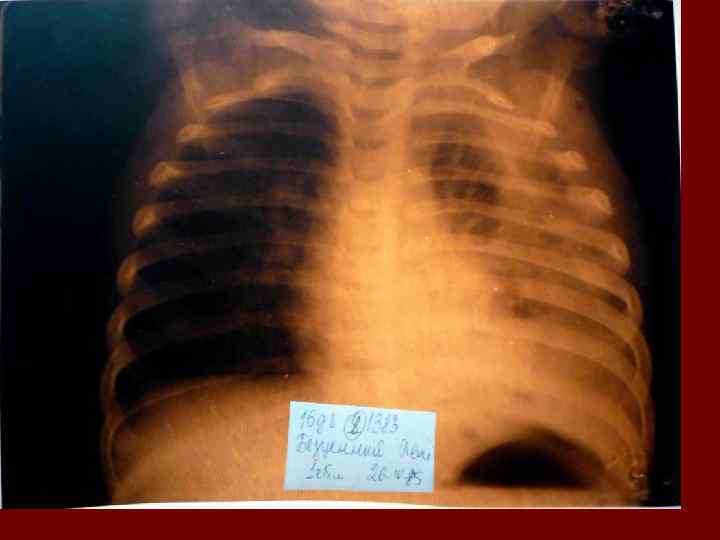

Пневмония Воспалительный процесс в респираторных отделах легкого с наличием внутриальвеолярной экссудации. n Это острое инфекционное заболевание легочной паренхимы, диагностируемое по синдрому дыхательных расстройств и/или физикальным данным при наличии очаговых или инфильтративных изменений на рентгенограмме. n Пневмония – это, прежде всего, клинический диагноз, который ставит врач у постели больного, и только затем подтверждает рентгенологически. n

Пневмония - это неспецифическое воспаление легочной ткани, в основе которого лежат инфекционный токсикоз, дыхательная недостаточность, водно – электролитные и прочие метаболические нарушение с патологическими изменениями во всех органах и системах детского организма. Заболевание диагностируется на основании синдрома дыхательных расстройств и/или физикальных данных и верифицируется рентгенологически выявлением инфильтративных изменений в легких.

Долевая пневмония характеризуется лобарным пневмоническим инфильтратом. Крупозная ( пневмококковая) пневмония диагностируется прежде всего по клиническим данным. Крупозная пневмония сохраняет свою типичную картину пневмококковой пневмонии: острое начало с характерными клиническими данными, циклическое течение, несклонность к деструкции, гомогенной и лобарной инфильтративной тенью при рентгенологическом исследовании. Вместе с тем, широкое использование антибиотиков способствовало значительному снижению числа крупозных пневмоний у детей. Интерстициальная – редкая форма пневмоний, при которой оказывается поражен прежде всего интерстиций. Как правило, интерстициальная пневмония обусловлена вирусами, пневмоцистами, внутриклеточными микроорганизмами и грибами.

Морфологическую форму пневмонии определяют по клинико – рентгенологическим данным: выделяют очаговую, очагово – сливную, долевую ( крупозную), сегментарную и интерстициальную пневмонии. Очаговая – наиболее распространенная форма. Пневмонические очаги чаще бывают размером 1 см и более. Очагово – сливная – инфильтративные изменения в нескольких сегментах или во всей доле легкого, на фоне которых могут быть видны более плотные участки инфильтрации и/или полости деструкции. Сегментарная – в процесс вовлекается весь сегмент, который, как правило, находится в состоянии гиповентиляции, ателектаза. Морфологическая картина воспаления при очаговых и сегментарных пневмониях связана с первичным инфекционным воспалением в бронхах, что дает основание отнести эти варианты поражения легочной ткани к бронхопневмониям, нередко сопровождающихся бронхообструктивным или бронхообтурационным синдромами. В настоящее время данный тип пневмоний у детей встречается наиболее часто.